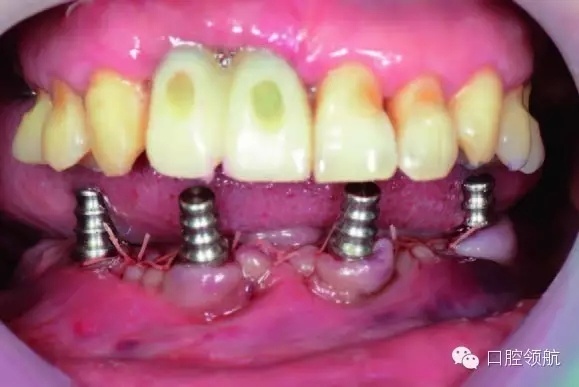

植入4顆NobelActive™,后部為RP4.3*15,前部為RP4.3*13。安放閉口轉移桿(圖6-9,圖6-10)。

圖6-9 術中拔除10顆患牙

圖6-10 下頜植入All-on-4 后口內照